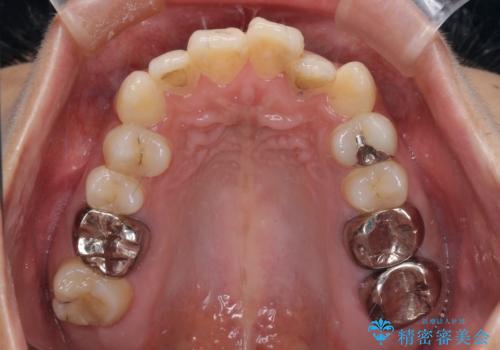

- 口元の閉じにくさを気にして来院された患者様です。

上下ともに歯列が前方に突出していたため、上下左右の第一小臼歯4本を抜去し、ワイヤー装置による矯正治療を行うこととしました。

舌の突出癖による影響もあったため、舌のトレーニングを並行して実施しました。

左下奥歯にむし歯が認められるため、矯正治療後にセラミックインレーにて修復治療を行うこととしました。